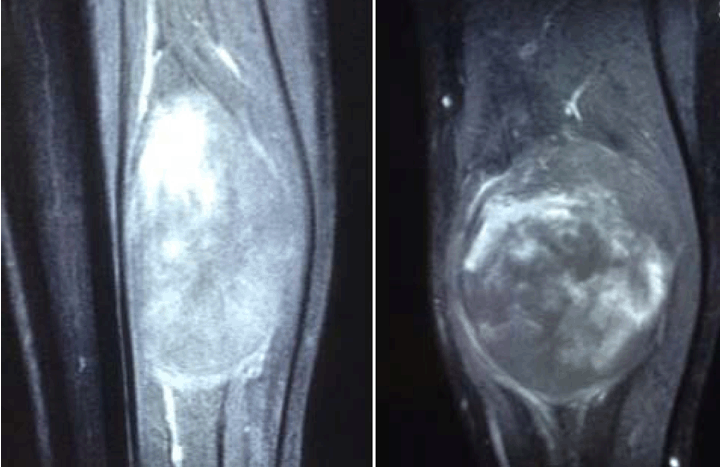

A 37-year-old white male presented himself with a slowly growing mass in his left calf. He was complaining of mild pain and paresthesia of 12 months duration. Loss of sensation in the sole of the foot was observed. On physical examination, a firm painful mass was palpable in the posterior compartment of the left calf. The tumor was relatively mobile in relation to adjacent structures. Also the pain was exacerbate by the motion and prolonged orthostatism. Laboratory testing showed no alteration of erythrocyte sedimentation rate (ESR), C-reactive protein (CRP), fibrinogen or alkaline phosphatase (ALP). The X-ray of lungs was normal. In magnetic resonance imaging (MRI) scan the lesion appeared to be ovalar and multinodular. It measured 90x71x46 mm occurring the distal third of calf posterior compartment. There was a high intensity signal in T2-weighted images and low intensity signal in T1-weighted images (Figure 1). No invasion of the surrounding bones was observed.

Figure 1: T1-weighted Magnetic resonance imaging scans of tumor.